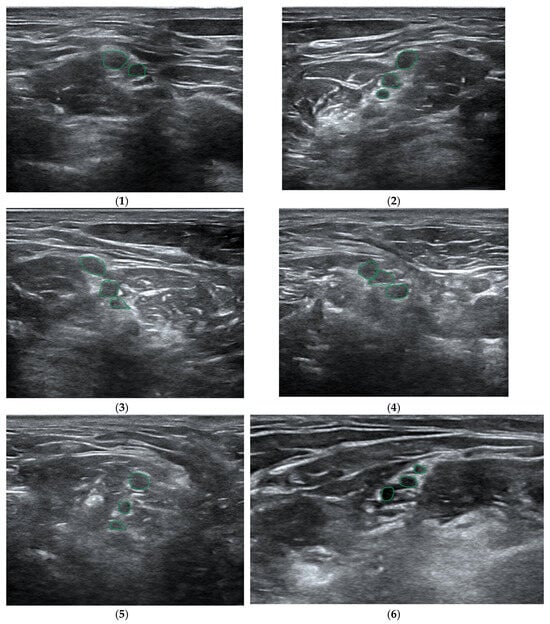

- Gungor, I.; Gunaydin, B.; Oktar, S.O.; Buyukgebiz, B.M.; Bagcaz, S.; Ozdemir, M.G.; Inan, G. A real-time anatomy identification via tool based on artifcial intelligence for ultrasound-guided peripheral nerve block procedures: An accuracy study. J. Anesth. 2021, 35, 591–594. [Google Scholar] [CrossRef]

- Erdem, G.; Ermiş, Y.; Özkan, D. Artificial intelligence-powered ultrasound guided regional nerve block in three patients: Case report. J. Turk. Soc. Algol. 2023, 35, 167–171. [Google Scholar] [CrossRef]